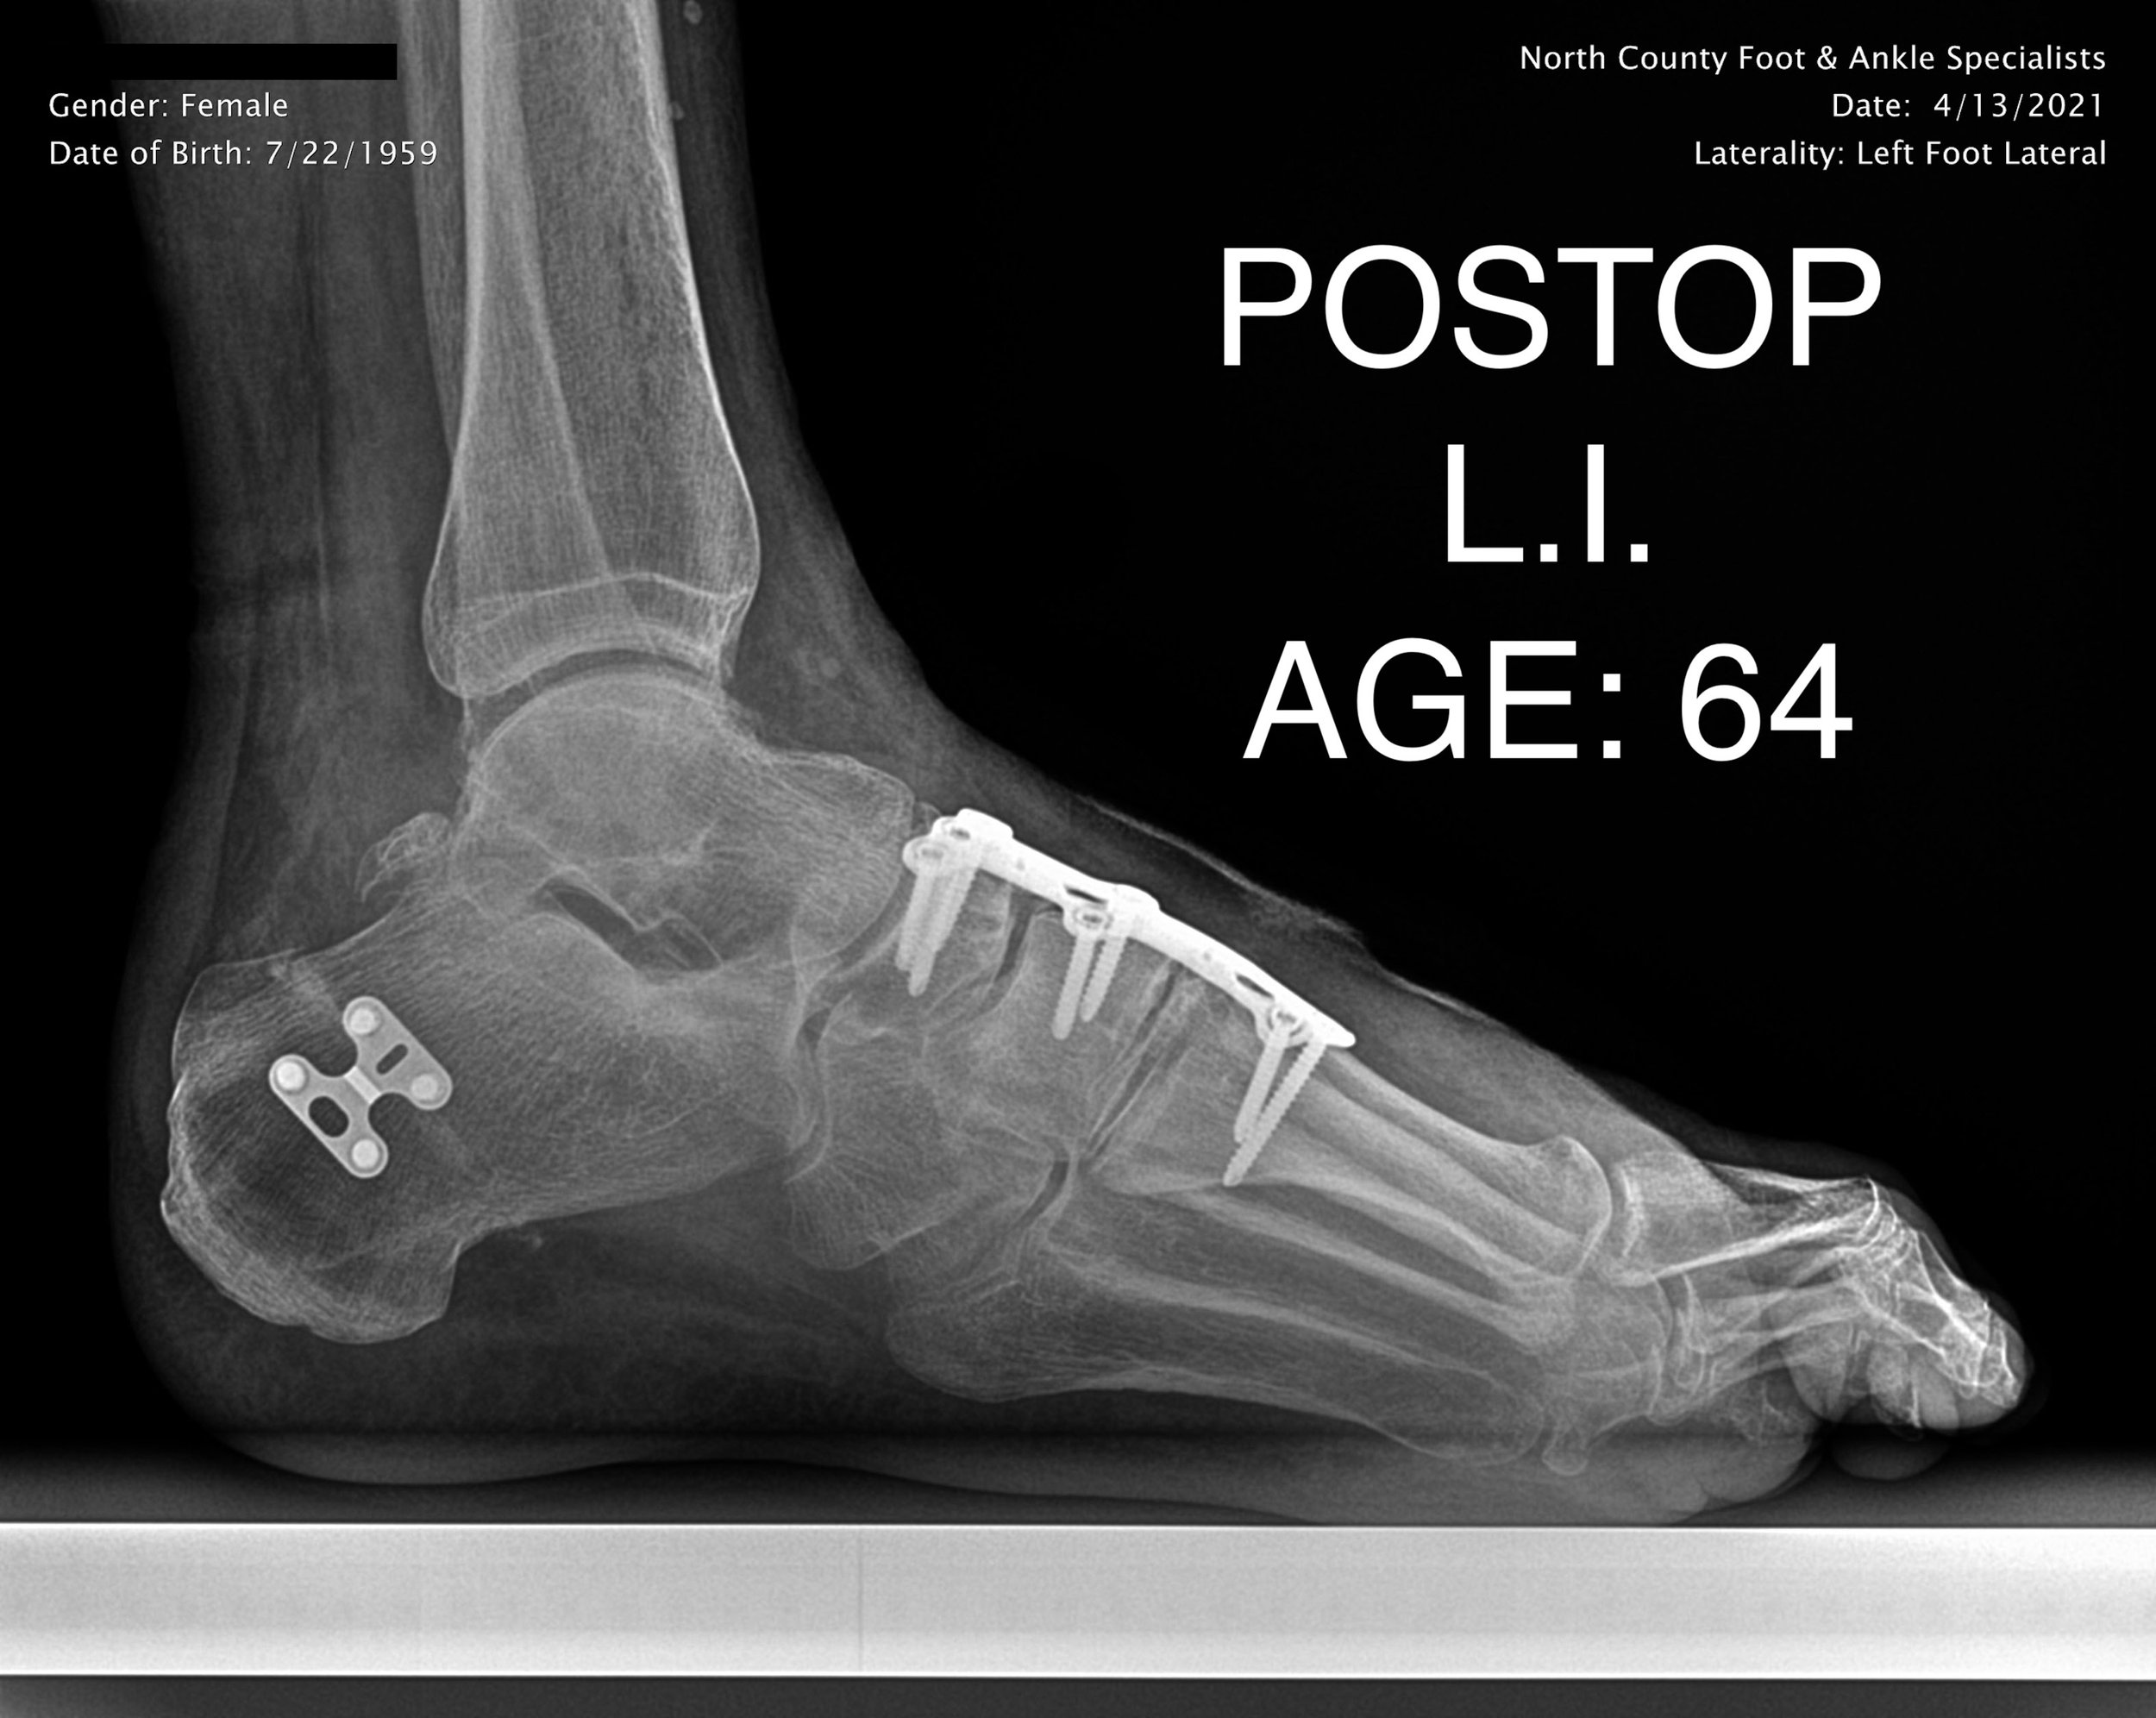

ADULT FLAT FOOT RECON